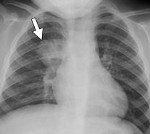

Рентгенологическая картина при очаговой пневмонии может быть вариабельна. В типичных случаях с помощью рентгенографии легких определяются очаговые изменения на фоне периваскулярной и перибронхиальной инфильтрации. В сомнительных случаях рентгенологические данные должны уточняться с помощью КТ и МРТ легких, бронхоскопии.